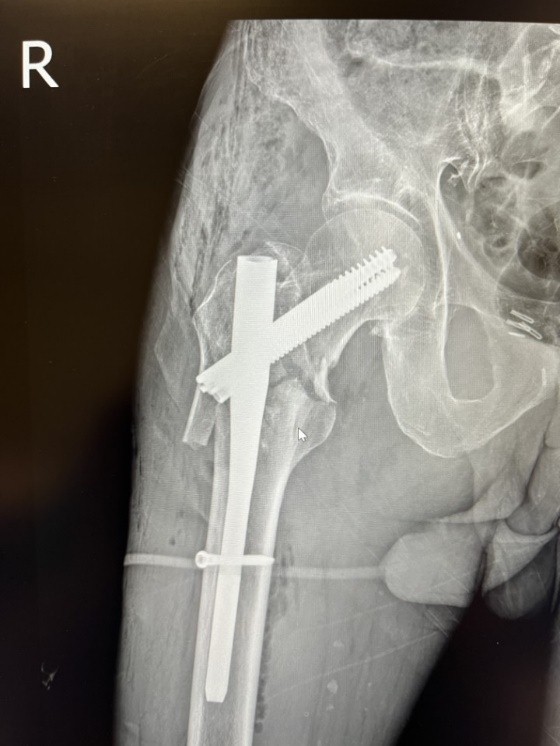

The computed tomography trauma series revealed vertebral osteoporotic fractures of TH12, L1, and L3, which are not related to the acute trauma. He was given adequate painkillers, immobilized with a coxo-femoral cast bilaterally, and was admitted to the intensive care unit. After a short pre-operative preparation, he underwent operative treatment for both fractures on the day of admission, which was performed under general anesthesia. The patient was placed on a radiolucent traction table, and the right transtrochanteric fracture was first fixated with closed reduction and a non-reamed intramedullary short nail. After open reduction, the left subtrochanteric fracture was fixated with a non-reamed long nail with distal static locking screws. Fluoroscopic image controls were acceptable, and there were no intraoperative complications. Postoperatively, patient recovery was without complications; the only problem was non-complicated anemia (67 g/L), solved with two units of blood. On the 1st post-operative day, radiographic control was done (Figs. 2 and 3).

Figure 2: First post-operative day radiographic control of the right hip. Closed reduction and intramedullary fixation (InterTan 10×200).